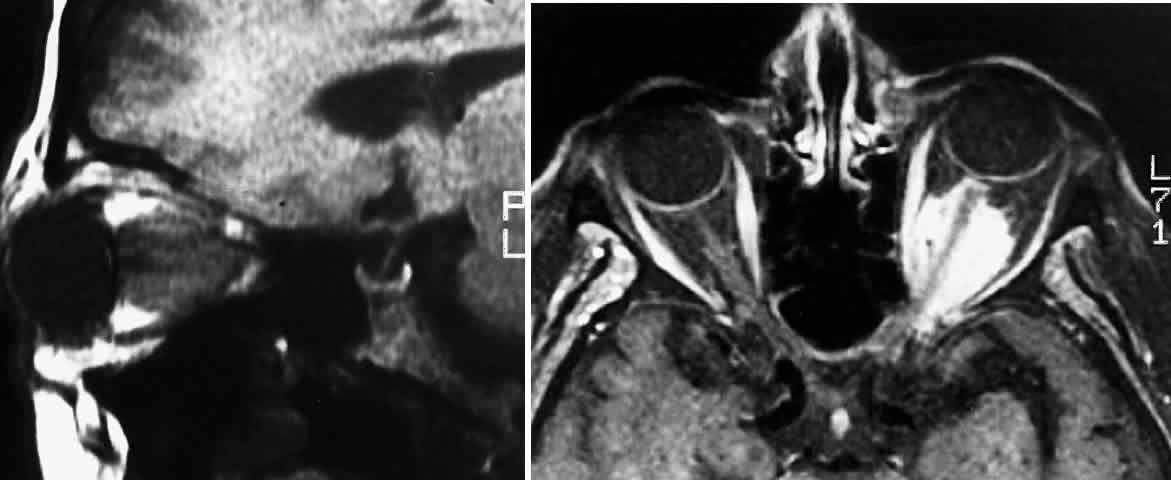

Proptosis is most common in patients with intraorbital tumors, although it can sometimes be observed in patients with concomitant chiasmal and intraorbital involvement3 (Figs. 1 and 2). Proptosis can be the presenting sign in glioma patients, and may even precede visual loss.13 Pain associated with the proptosis is not characteristic of optic gliomas.4 Minimal to severe proptosis, generally nonpulsatile and axial in nature, has been described, but it is typically in the range of 2 to 4 mm. Severe proptosis may jeopardize the health of the globe; it may also be a major cosmetic problem. The tumor itself is usually not palpable. Standardized A-scan examination of optic nerve gliomas demonstrates echograms of regular, homogeneous, low-to-medium reflectivity. On B-scan examination, large optic nerve gliomas appear as fusiform masses replacing the optic nerve void.41 In contrast to optic gliomas, meningiomas are typically irregular in structure and demonstrate higher internal reflectivities.41,42 The 30° test is usually negative when performed on gliomas because of the solid infiltration of the nerve; however, positive tests have been noted, suggesting perioptic subarachnoid fluid surrounding the tumor.42

Fig. 1. Five-month-old infant presenting with progressive proptosis caused by an optic pathway glioma. There is mechanical restriction of the motility of the affected right eye.

Fig. 2. Contrast-enhanced T1-weighted axial MRI of the orbits of the patient in Figure 1, demonstrating a large optic pathway glioma with posterior extension into the optic tracts and radiations. (Courtesy of Orlando Ortiz, MD, and Jeffrey Hogg, MD)